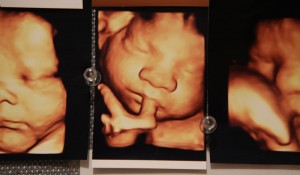

She added that by 20 weeks she sees all kinds of hand movements including what appears to be baby waves and thumb-sucking.

“At 20 weeks you see much more controlled movements,” Burnett said. “They are rolling, sucking their thumb, and their hands are constantly in their faces, especially when we are trying to analyze facial anatomy.”

“I think parents want it to be so personal,” said ultrasound tech Shelly Kemppel, who often types, ‘hi mom,’ or ‘peace’ on their personal picture. “It simply adds to their joy.”